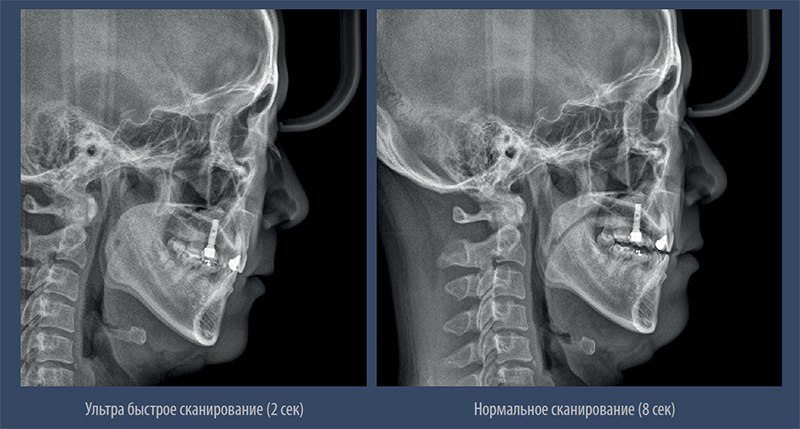

Цефалометрия

Высокое разрешение съёмки ТРГ

– Быстрый режим позволяет получить качественное цефалометрическое изображение без артефактов движения и искажений